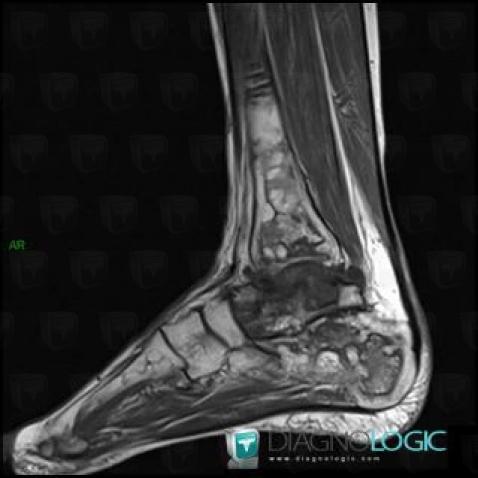

Avascular necrosis, Calcaneus, MRI

Here is the specific information in the key image above:

- Diagnosis Avascular necrosis, Location(s) Calcaneus, with gamuts Osteolytic lesion of calcaneus, T1 WI Hyperintense bone lesion, Lucent lesion in foot

Avascular necrosis, Tibia - Distal part, MRI

- Diagnosis Avascular necrosis, Location(s) Tibia - Distal part, with gamuts Well-defined osteolysis, Epiphyseal osteolysis

- Diagnosis Gaucher disease, Location(s) Tibia - Distal part, with gamuts Mulltiple osteolysis